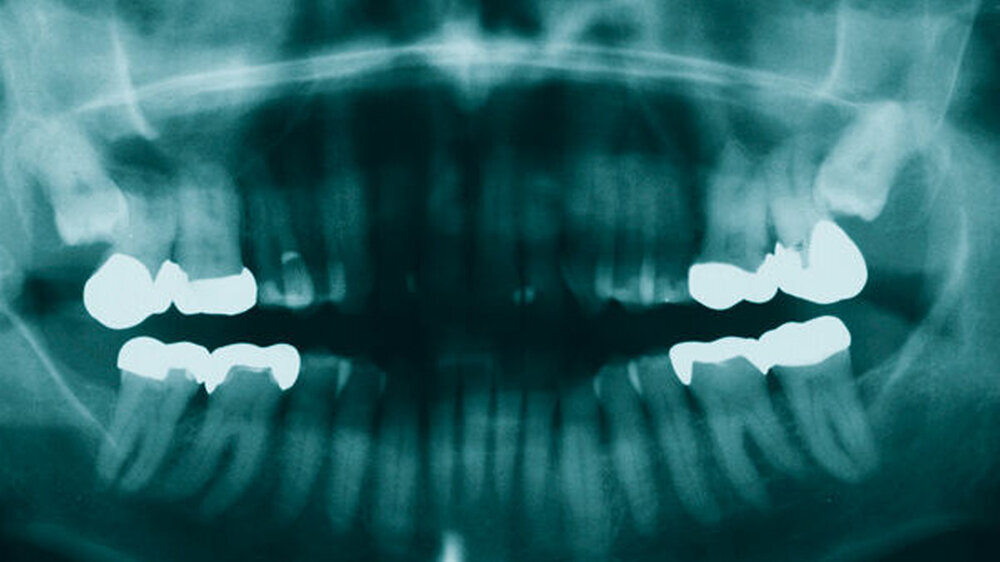

Die Therapie der chronischen Sinusitiden blieb erfolglos, so dass der Patient an täglicher, beidseitiger Exkretion grünlichen Sekrets aus den Nasenlöchern sowie chronischen Kopfschmerzen litt. Dental waren alle Oberkieferzähne klinisch unauffällig und vital. Zum Ausschluss einer klinisch okkulten dentogenen Ursache der chronischen Sinusitis maxillaris und zur Beurteilung der Lage der retinierten Zähne 18 und 28 wurde eine Panoramaschichtaufnahme (PSA) erstellt.

Nebenbefundlich zeigte sich in der PSA (Abbildung 1) im Bereich des rechten Kieferastes eine circa 10 mm x 6 mm große, klar begrenzte, knochendichte Opazität. Diese Opazität erschien als am Rand opak verdichtete und nicht infiltrierende Struktur, die mit keiner erkennbaren dentogenen oder nicht-dentogenen Struktur direkt korrelierte. Auf einer zum Vergleich vom Hauszahnarzt angeforderten PSA, die etwa neun Jahre zuvor erstellt wurde, ist ein vergleichbarer Befund zu sehen (Abbildung 2).